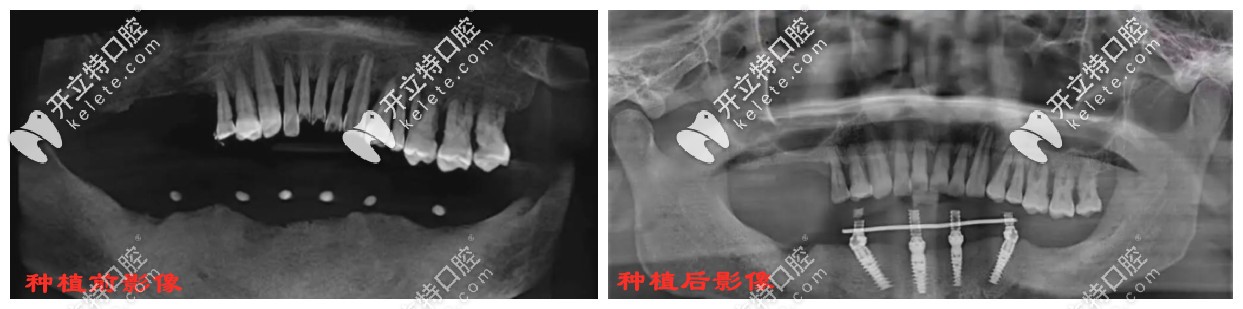

雅度口腔一顧客種植all-on-4前后影像對比▼

種植牙前后影像對比